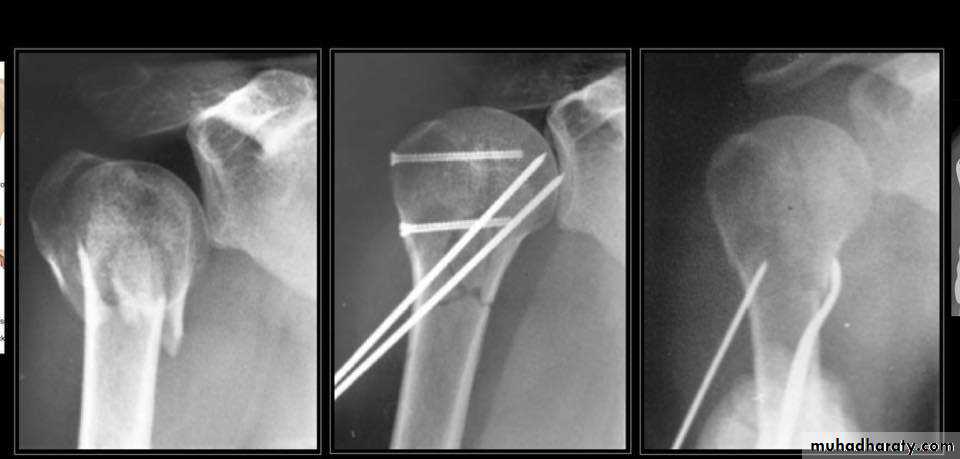

• Close reduction (MUA&sling ) 6weeks and active exercise later if failure

• Open reduction & internal fixation by percutaneous pinning plate and screws or intramedullary nailing21

TREATMENT

30

ORIF

TRATMENT IN YOUNG

35